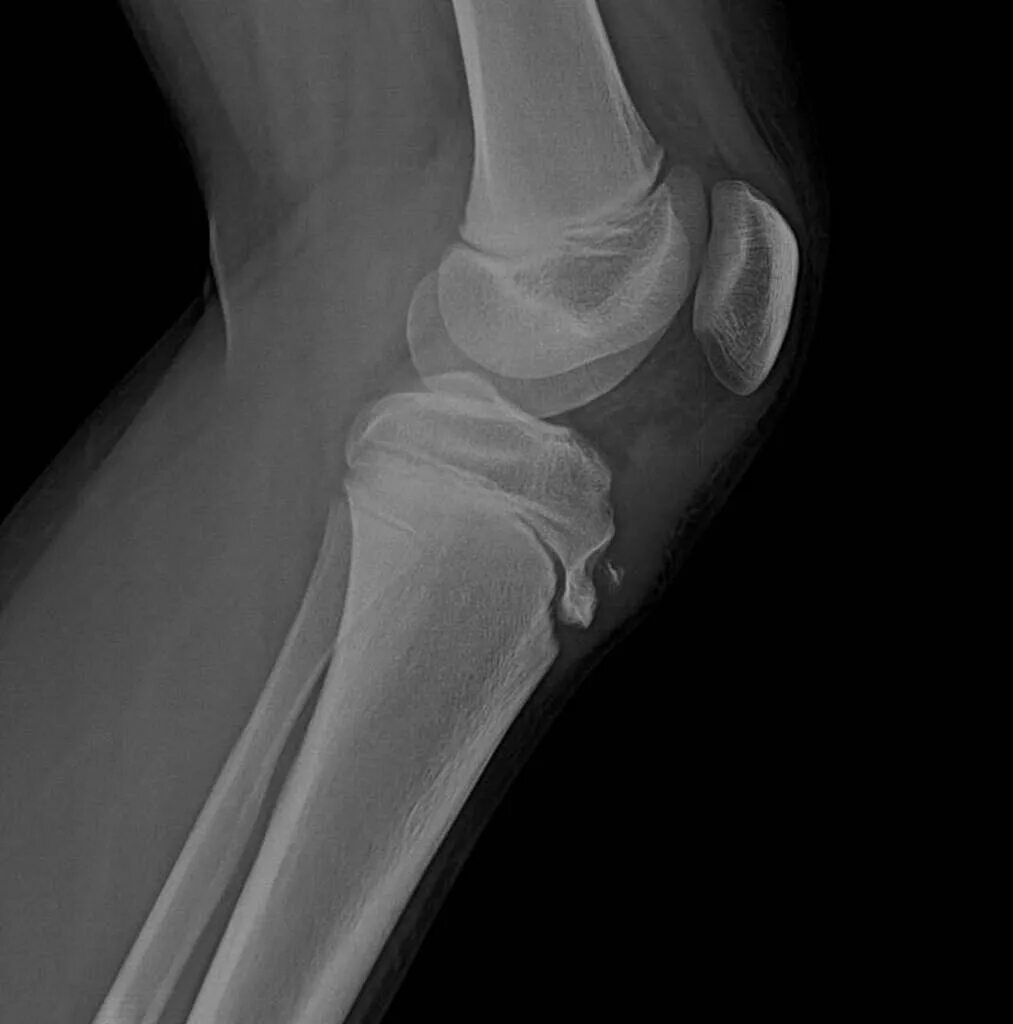

Болезнь осгут шляттера